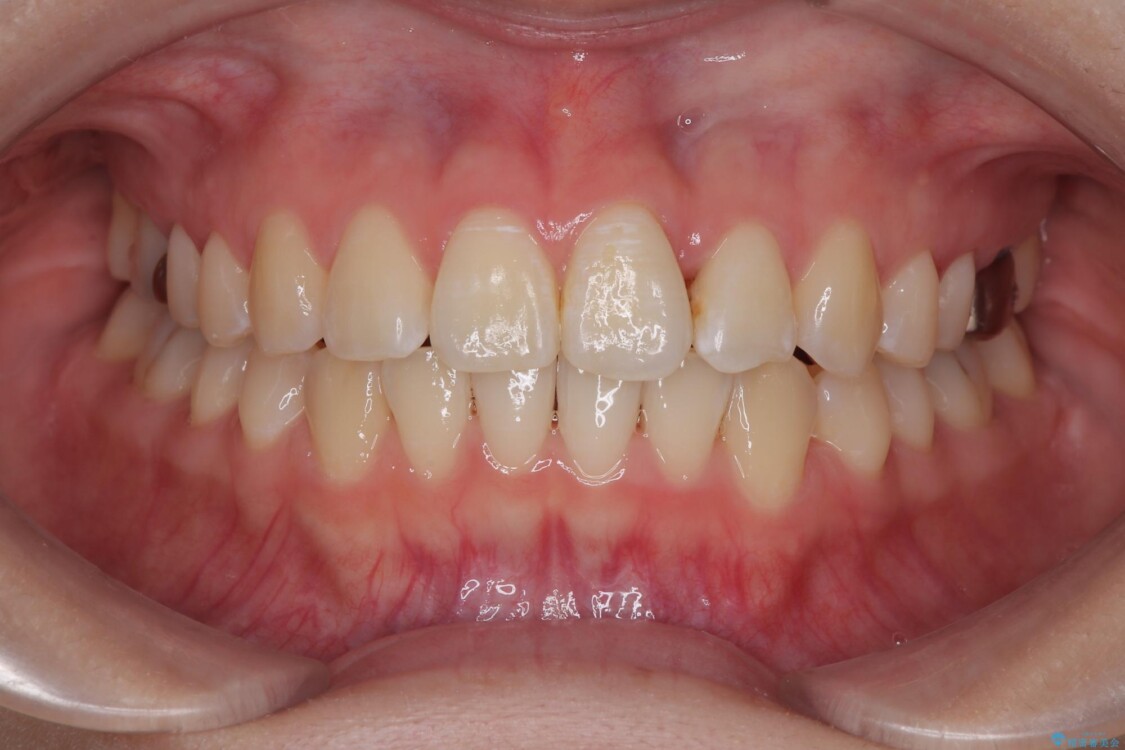

「前歯のねじれを改善したい」とのご希望で当院に来院された患者様です。

診察の結果、上下の前歯部に**叢生(そうせい/歯のガタガタ・重なり)**が認められました。

特に上の前歯にはねじれや重なりがあり、審美的にも清掃性にも影響している状態でした。

治療前

• 前歯のねじれ・ガタガタを10か月で改善!20代女性の矯正治療|クリアブラケットでむし歯になりにくい歯並びへ改善 治療前画像